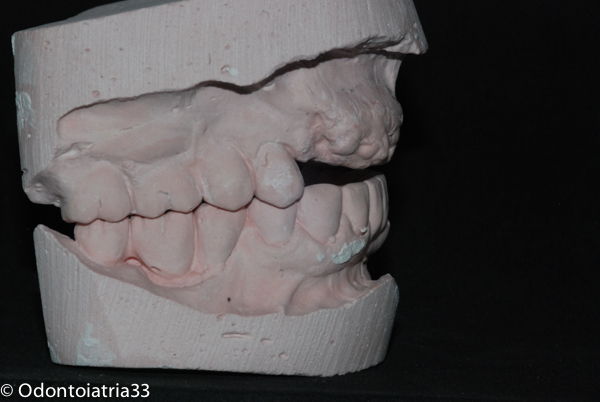

Si è deciso pertanto di procedere all'estrazione degli elementi dentari 13-12-11-21-23 riabilitando per due mesi la paziente con un provvisorio mobile in acetato. Contrariamente a quanto succede normalmente dove la problematica maggiore con cui fare i conti è il quantitativo osseo ridotto e di conseguenza l'aumentata distanza interarcata, in questo caso ci siamo trovati a dover affrontare un ridotto spazio interarcata con rapporti intermascellari sfavorevoli in senso antero-posteriore oltre che cranio-caudale.

Trattandosi di guidare al contrario la morfologia ossea tramite rimodellamento abbiamo cercato di trovare un equilibrio fra necessaria riduzione ossea in senso volumetrico antero-posteriore /cranio-caudale e perdita di supporto sul labbro superiore con appiattimento del profilo, posizionando gli impianti un po' più vestibolarizzati e profondi,nonchè lavorando sui profili gengivali mediante provvisori a condizionamento tissutale.

I primi provvisori avvitati sono stati posizionati dopo 6 settimane dall'intervento chirurgico di inserimento implantare e rimodellamento. I provvisori avevano ancora per ragioni tecniche un rapporto di overjet da correggere poi con i definitivi.